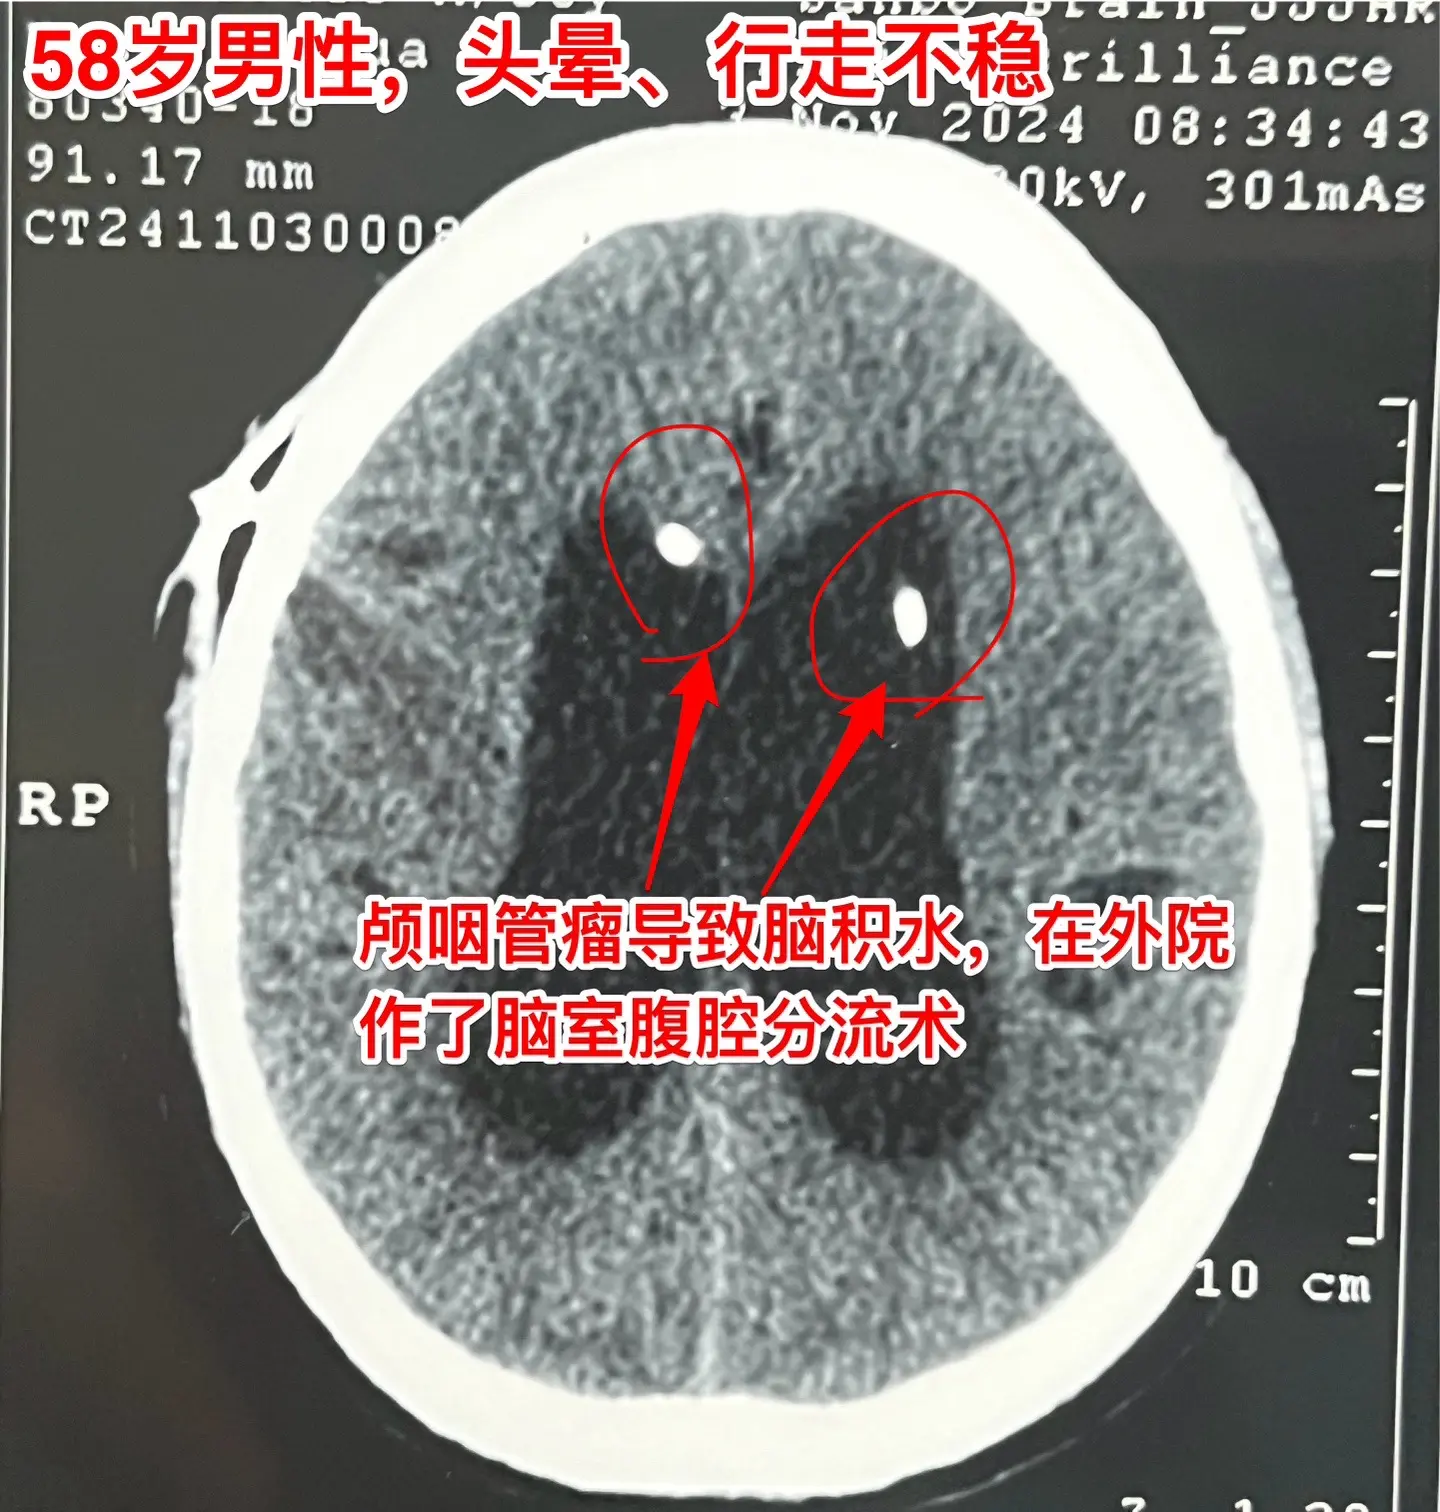

颅咽管瘤内出血(瘤卒中)属于罕见现象。有些脑部肿瘤容易出血,称之为瘤卒中,比如垂体瘤(属于良性肿瘤)和高级别胶质瘤,而颅咽管瘤发生瘤卒中的可能性却很小很小。 58岁的南通市男性,九年前体检发现鞍区病变,无任何症状,一直没有做任何治疗。四个月前开始出现头晕、行走不稳,同时还有思维糊涂,有一次癫痫发作。这次到医院检查就发现鞍区肿瘤增大了,而且导致了脑积水。 2024.9在外院作了脑积水的分流手术,没有切除肿瘤。手术后行走不稳症状有好转,但是思维糊涂症状却越来越严重,有时感头痛。 2024.10到我科住院,病人不仅仅是思维糊涂,还出现头痛症状。行头部CT检查提示颅咽管瘤内出血了。 2024年11月14日作了开颅手术。切除肿瘤过程中可以看见肿瘤内有陈旧出血。病理报告为乳头型颅咽管瘤。乳头型颅咽管瘤出现瘤卒中的概率是很低的,我曾经在2008年报告了一例。造釉细胞性颅咽管瘤几乎不出现瘤卒中。 这个病人的脑积水是由颅咽管瘤引起的,所以,切除颅咽管瘤后脑积水自然就会缓解。希望他的症状会越来越改善。颅咽管瘤脑积水瘤卒中